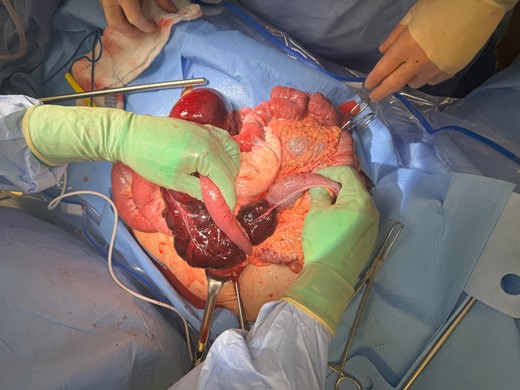

The patient was taken for emergent exploration. Upon entry to the abdomen, a large amount of purulent drainage was encountered. The cecum and terminal ileum were in the left upper quadrant, and it became clear that this was an internal hernia through Petersen’s defect (Fig. 2). The right colon and terminal ileum were necrotic, the hernia was reduced, a right hemicolectomy was performed, the patient was left in discontinuity, and a temporary closure device was placed to perform a second look 24 hours after the index surgery. At her second surgery, a stapled ileocolic anastomosis was created, the Petersen’s defect was closed with an absorbable running suture, and the abdomen was closed. The patient recovered without complication and was discharged home on postoperative day 5.